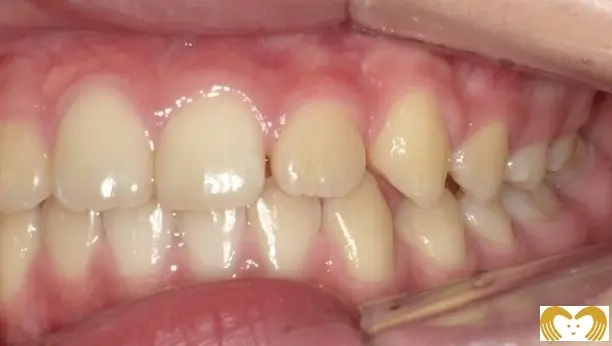

症例02:交叉咬合

《Before》

《After》

- 年齢:

- 7~12歳

- 性別:

- 女の子

- 治療内容:

- ネオキャップシステムによる、交叉咬合の治療

- 治療回数・期間:

- 約5年間

- 治療費:

- 495,000円(税込)

- リスク:

- 取り外し可能な装置の為、治療の効果が使用頻度に左右されます。